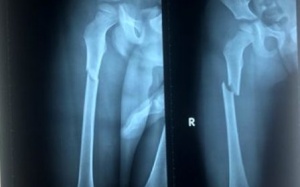

Nhập viện trong tình trạng đau đớn dữ dội, bầm từ đầu đến chân, qua kết quả kiểm tra hình ảnh, bác sỹ xác định bệnh nhi bị gãy xương đùi bên phải. Nguyên nhân ban đầu được...